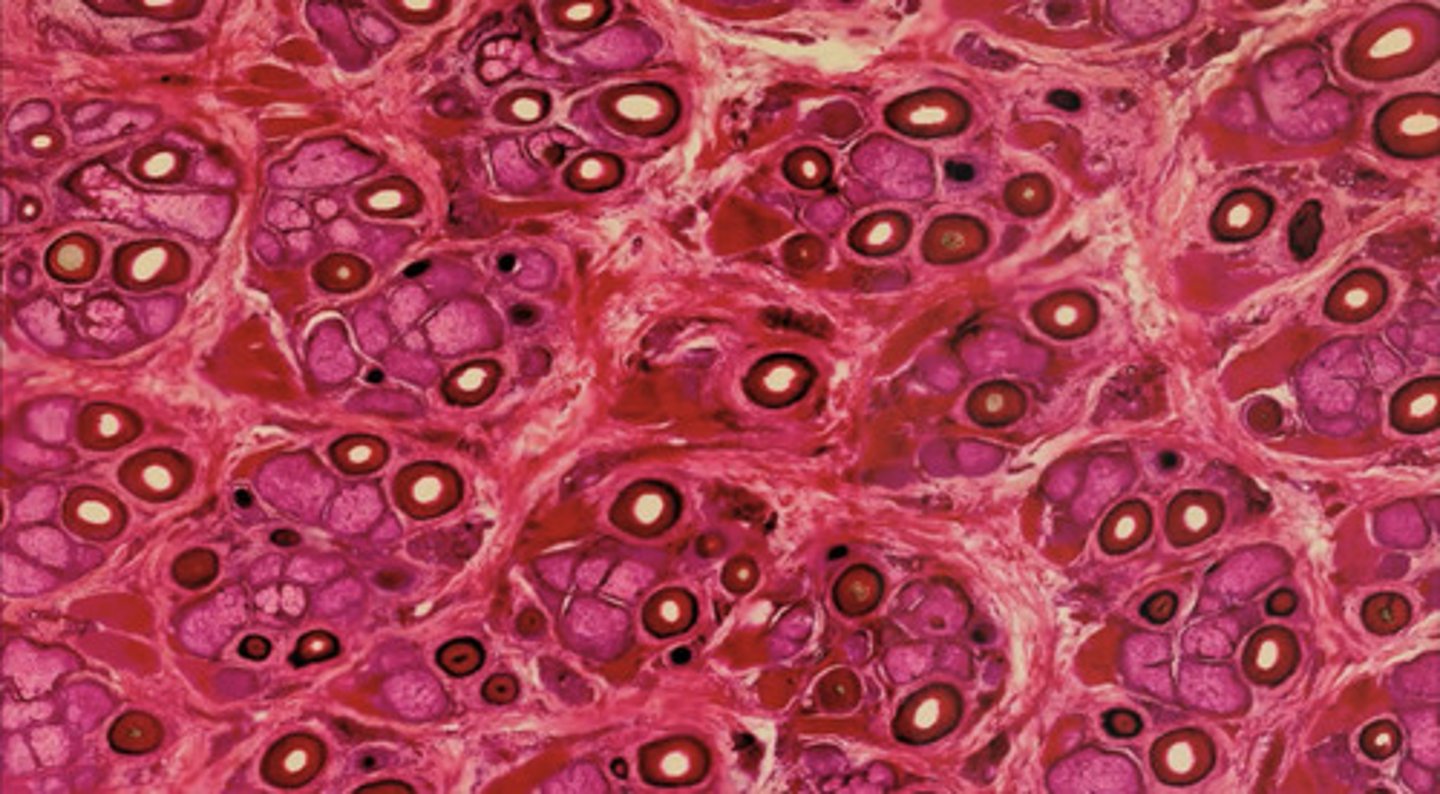

Skóra owłosiona - przekrój poprzeczny (H+E)